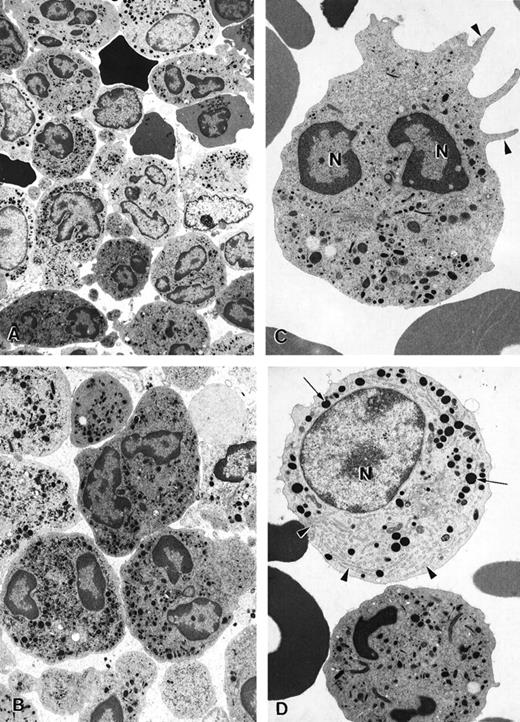

The ultrastructure of bone marrow cells from patient 2 and a healthy volunteer donor was investigated before and during G-CSF therapy using electron microscopy (Figure 4). The bone marrow aspirate from a healthy volunteer contained predominantly neutrophils at various stages of maturation and immature red blood cells (Figure 4A; arrowheads). Few degenerating cells and minimal cellular debris were observed. In contrast, numerous degenerating cells (indicated by arrows) were present in the bone marrow aspirate from a patient with myelokathexis. In the degenerating cells, typical features of apoptosis were present, including the convoluted nucleus in an otherwise still intact cell. The granules (G) were aggregated, and the heterochromatin was concentrated in distinct, dense granular patches located on the inner surface of the nuclear membrane (Figure 4B). At higher magnification, apoptotic features such as cytoplasmic blebbing (arrowheads) and intense condensation of chromatin in the nucleus (N) were readily apparent in neutrophils (Figure 4). Macrophages were observed with numerous phagosomes that contained cellular debris as a result of phagocytizing senescent cells (Figure 4D). These apoptotic features were not present in the bone marrow aspirate from a healthy volunteer. These data indicated that accelerated apoptosis occurs in vivo in the myeloid precursor population in patients with myelokathexis.

Electron micrographs of bone marrow from patient 2 before granulocyte colony-stimulating factor treatment.

(A) Low magnification of the bone marrow shows degenerating cells (*), few mature neutrophils (**), and promyelocytes (arrows). Neutrophils with convoluted nuclei (arrowheads), a sign of early apoptosis, are observed. Magnification ×4000. (B) Macrophage in the bone marrow contains several phagosomes (arrows) with cellular debris of neutrophils. Neutrophil (arrowheads) with a distinguishable nucleus (*) and granules is discernible in 1 of the phagosomes. N, macrophage nucleus. Magnification ×6500. (C) Neutrophil in an early stage of apoptosis. The nucleus is convoluted (arrowheads), and the chromatin is condensed and distinctly circumscribed, forming dense granular masses (*) along the inner surface of the nuclear envelope. Magnification ×7500. (D) Neutrophil in a later stage of apoptosis. The cell shows cytoplasmic blebbing (arrowheads) and cellular fragmentation (arrow). N, nucleus. Magnification ×13,000. (E) Promyelocytes observed in the bone marrow. The cell at the bottom left appears normal and has a large, round nucleus (N), numerous granules, and a well-developed rough endoplasmic reticulum (arrows). The cell at the top right is apoptotic, as indicated by the fragmented nucleus (*), and has distinct areas of condensed chromatin (arrowheads). Magnification ×5500.